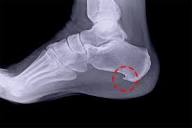

Topuk dikeni ilerlememiş evresindeyse muayene ile tanı konulabilir. Ayrıca MR ve bazen Ultrason görüntüleme ile taban zarındaki ödem ve kalınlaşma tespit görüntülenebilir.Basit bir röntgen ile de tanı koyulabilir.